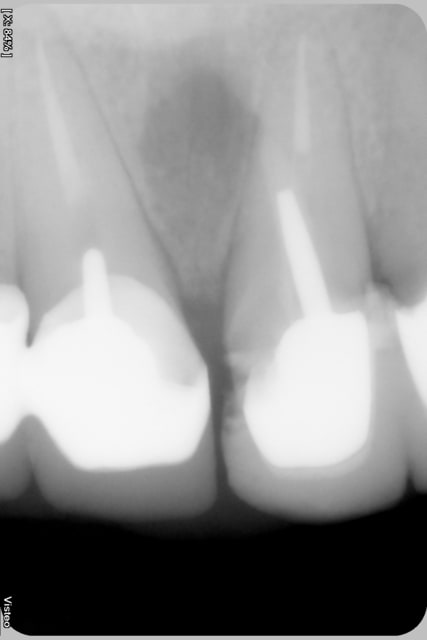

En voulant faire une ccm sur une 21, lors de l'alésage pour gagner un peu de longueur j'ai fait un faux canal en direction mésial..

Je me suis rendu compte de ce faux canal 1 semaine après lors de l'essage du pivot, le patient se plaignait de douleurs également...

J'ai utilisé du mta et et mis en place le pivot dans la foulée...

je pense malheureusement que c'est mal parti cher confrère... laisse en provisoire et évalue la cicatrisation la nature est parfois bonne fille mais là dis donc t'es vraiment pas dans l'axe radiculaire... il y aura toujours des risques énormes de fracture radiculaire sur cette dent. comme dirait céramik... implant...

Pour ce qui est du mta (on va imaginer qu'on a cette fois une dent avec une racine longue), personnellement, je l'aurais mis en place dans la lésion et laisser cicatriser sans mettre le "pivot", j'aurais fait un bridge collé en provisoire (et en catastrophe) en expliquant bien au patient qu'ayant fait quelque chose d'imprévu (enfin sans le tourner comme ça non plus), on ne pouvait pas poser la couronne comme ça. Une fois que ça aurait cicatrisé, j'aurai refait mon forage cette fois bien dans l'axe

Pendant une semaine le sang a contaminé ton canal, pas de phase d'hydroxyde pour désinfecter ce canal (et éventuellement commencer à recréer une barrière cémentaire), de plus le tenon n'est pas dans l'axe idéal du canal principal.